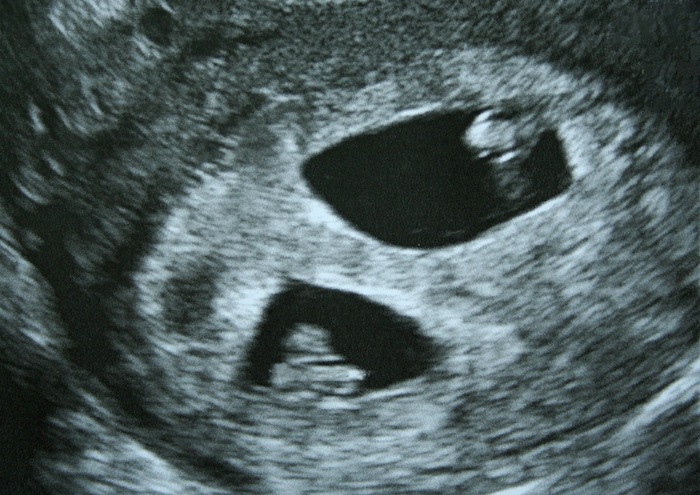

Here’s the big difference: in natural pregnancies, you’ve got no say over how many eggs your body releases or whether an embryo splits. With IVF, doctors control how many embryos go into your uterus. That’s why fraternal twins are way more common with IVF—about 90% of IVF twins are fraternal. So, could you tweak this process to guarantee twins? Let’s keep going.

The number of embryos transferred during IVF is the biggest factor in your twin odds. If your doctor puts two embryos in your uterus and both stick, bam—fraternal twins! In the past, transferring two or more embryos was super common because it boosted the chances of at least one implanting. Back in 2011, the twin rate with IVF was around 8.4%. But here’s the catch: today, doctors are leaning hard into single embryo transfers (SET). Why? Because twins come with risks (more on that later), and science has gotten so good that one high-quality embryo often does the trick.

In 2020, the IVF twin rate dropped to just 2.3%. That’s a huge shift! Clinics now transfer one embryo in over 90% of cases, especially for younger women with healthy eggs. So, while transferring two embryos ups your twin chances to about 25-30%, most doctors won’t do it unless there’s a good reason—like if you’re older or have had failed cycles.